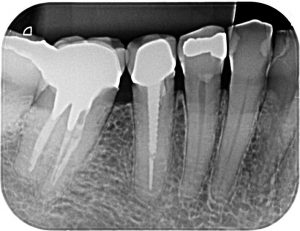

– Radiografia Periapical